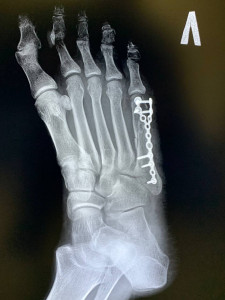

Добрый день. Мне 39 лет, получил перелом 5 плюсневой кости 3 ноября, 7 ноября прооперировали и поставили пластину. Сегодня сделал рентген 08.12.2025. Когда можно уже наступать на ногу и ходить. Срок 5 неделя наступила

Здравствуйте. По снимкам фиксация стабильная, но срок ещё небольшой. Полную опору обычно разрешают после контрольного осмотра и оценки сращения у вашего травматолога. Сейчас можно частичную нагрузку с опорой на пятку и в ортезе до решения лечащего врача.